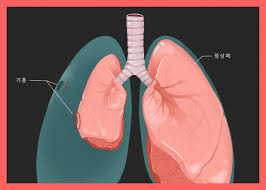

폐결절(pulmonary nodule)은 폐 안에 지름 3cm 이하의 작은 덩어리나 불투명 부위로, 흉부 X‑선이나 CT 검사에서 우연히 발견되는 경우가 많습니다. 대부분은 무증상이며, 양성인 경우가 많지만 일부는 악성(암)일 수 있어 주기적인 관찰이 필요합니다.